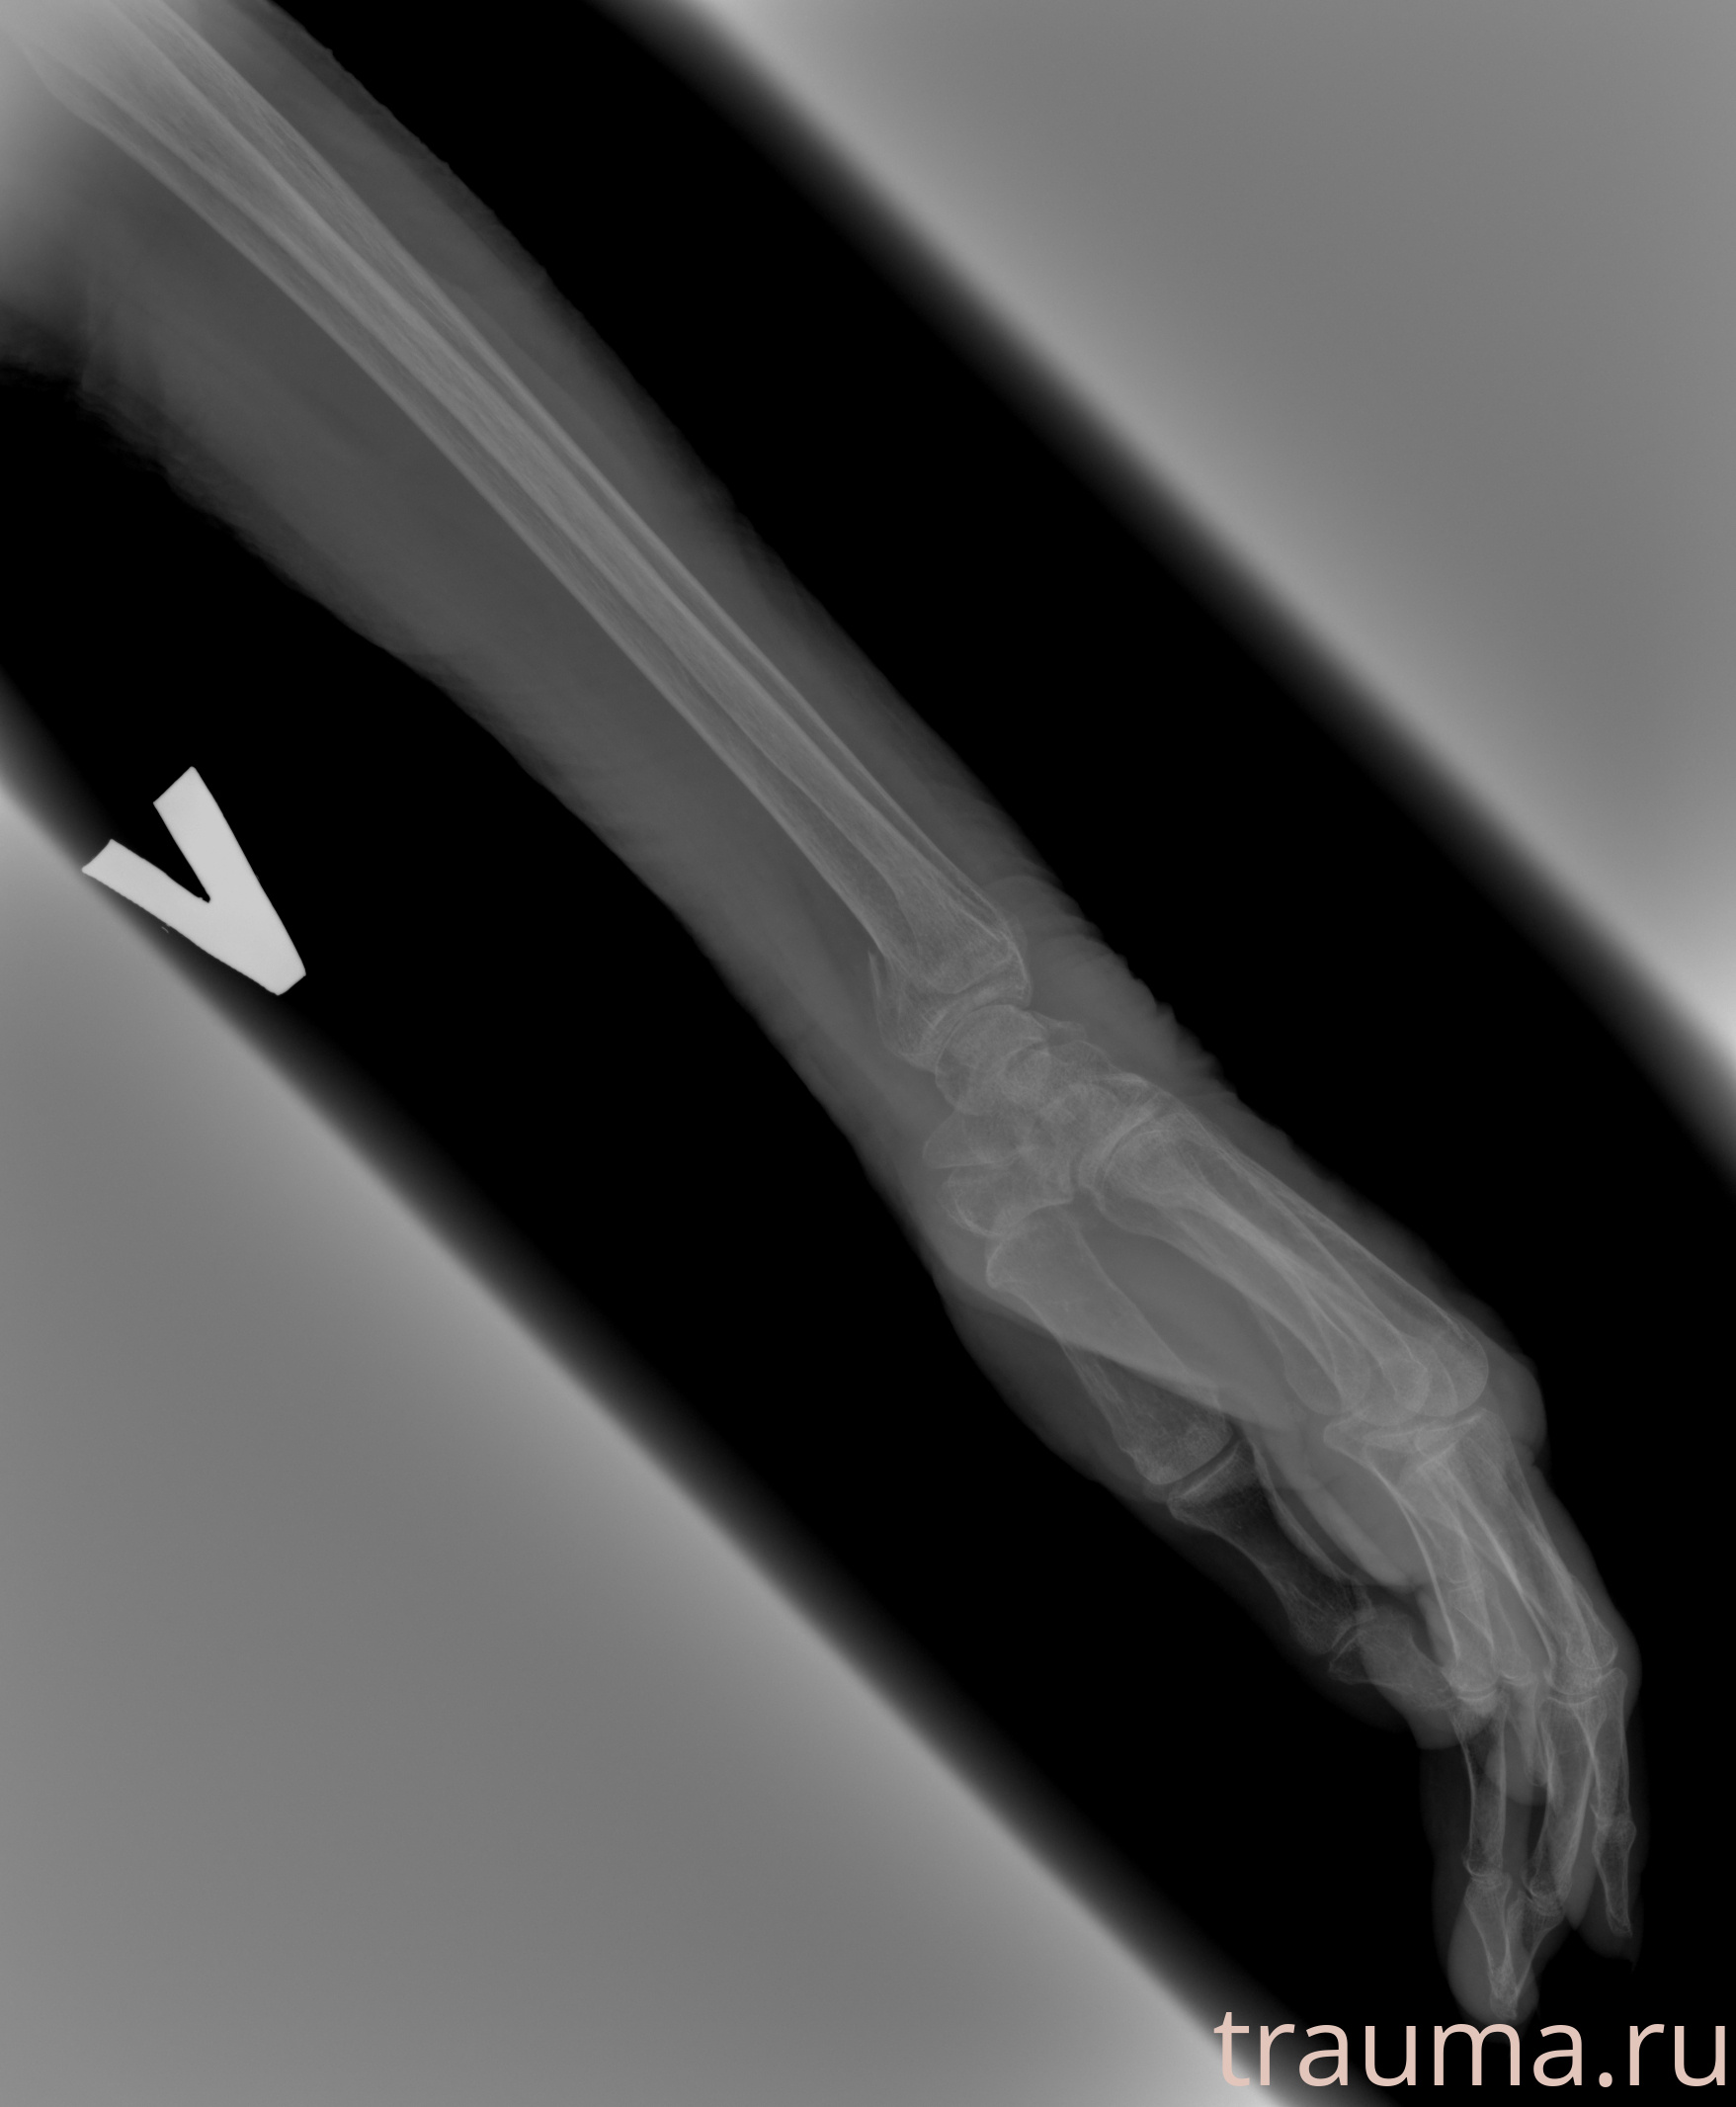

Рентгенограммы

Рентген на дому: по вашему адресу приезжает врач-рентгенолог, травматолог-ортопед с мобильным рентгеновским аппаратом, проводит диагностику травмы или заболевания, делает необходимые рентгенограммы, дает рекомендации по дальнейшему лечению. Получить качественные снимки в домашних условиях возможно благодаря уникальной методике, разработанной МосРентген Центром для института  Склифосовского